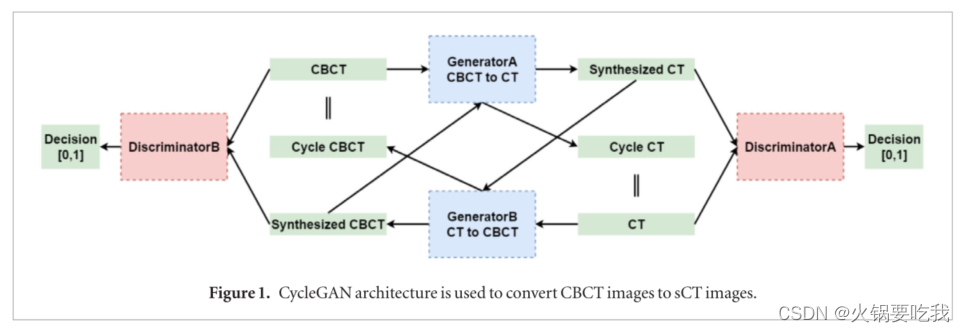

一、利用CycleGAN完成CBCT到CT的转换

LIANG, XIAO, CHEN, LIYUAN, DAN NGUYEN, et al. Generating synthesized computed tomography (CT) from cone-beam computed tomography (CBCT) using CycleGAN for adaptive radiation therapy[J]. Physics in medicine and biology.,2019,64(12):125002. DOI:10.1088/1361-6560/ab22f9.

目的:基于锥形束CT图像合成CT图像,并保留重要的解剖结构